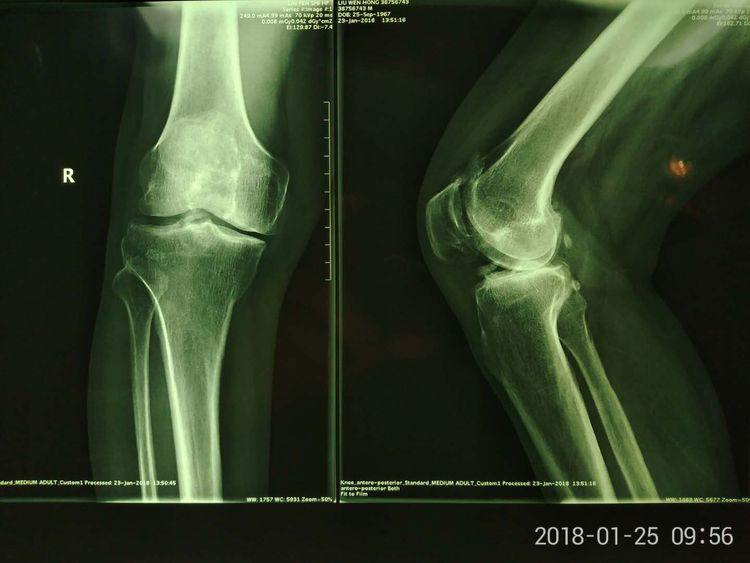

患者男,52歲,右膝關(guān)節(jié)疼痛、活動受限3年,加重1月。既往長期服用鎮(zhèn)痛藥物,近期關(guān)節(jié)腔內(nèi)注射玻璃酸鈉,膝關(guān)節(jié)疼痛癥狀進(jìn)行性加重,以致無法行走,患者為嚴(yán)重的膝關(guān)節(jié)內(nèi)翻畸形,保守治療無效,行膝關(guān)節(jié)置換術(shù)相對年齡較小,趙占富主任醫(yī)師決定采用"保膝"手術(shù)治療,膝關(guān)節(jié)內(nèi)外側(cè)切口均為4-5cm左右。

其適應(yīng)癥包括:1、膝關(guān)節(jié)內(nèi)側(cè)間室型骨性關(guān)節(jié)炎伴內(nèi)翻畸形,負(fù)重位X線片下肢力線測量內(nèi)翻角度5°-15°,存在膝關(guān)節(jié)內(nèi)側(cè)疼痛癥狀;2、外傷性膝關(guān)節(jié)內(nèi)翻畸形需矯正的患者。(骨創(chuàng)傷一科)